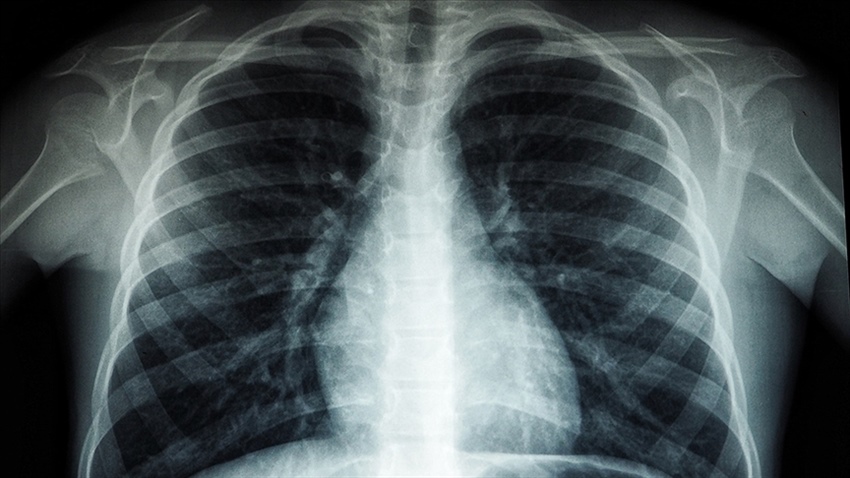

KOVİD-19 AKCİĞER KATILAŞMASINA NEDEN OLABİLİYOR

TÜRK TORAKS DERNEĞİ TÜBERKÜLOZ ÇALIŞMA GRUBU BAŞKANI PROF. DR. ŞEREF ÖZKARA: "(KOVİD-19) HASTALARIMIZIN ÖNEMLİ BİR KISMI İYİLEŞİYOR AMA BİR KISMINDA DA KALICI AKCİĞER HASARLARI OLABİLİYOR, AKCİĞER KATILAŞMASI YA DA İNTERSTİSYEL AKCİĞER HASTALIKLARI ORTAYA ÇIKABİLİYOR"